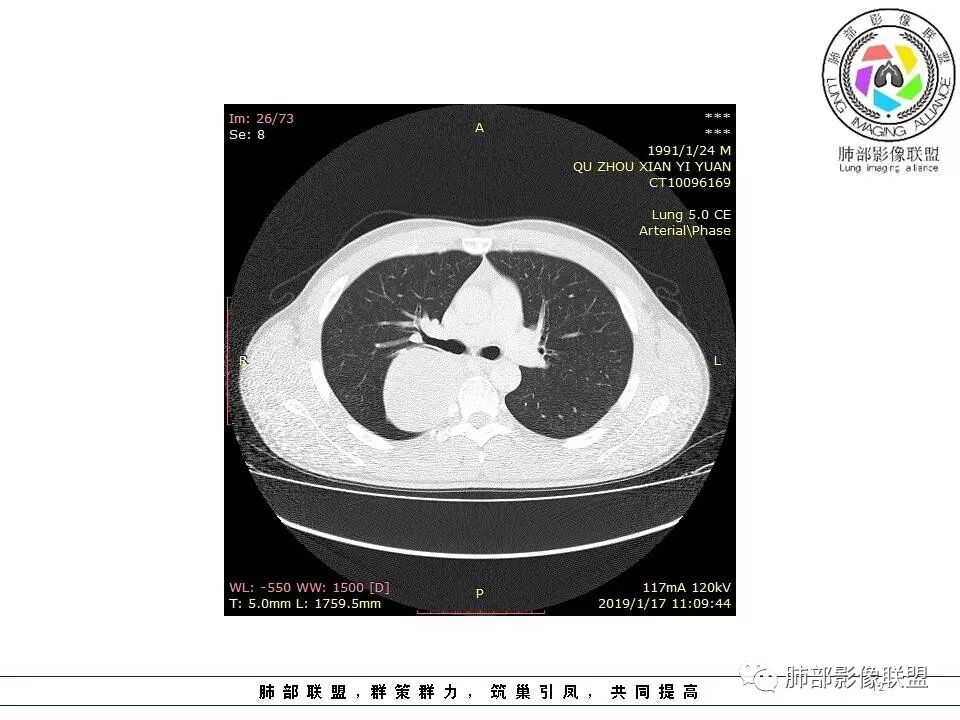

右后纵膈脊柱旁软组织占位,形态规则类圆,边缘光整,肺组织受压,胸膜尾,肋间动脉供血。中度不均匀延迟强化。

后纵隔脊柱旁占位性病变,疾病谱有神经鞘瘤,sft,节细胞瘤,髓外造血。此例有胸膜尾征,蛇纹征 ,延迟强化。考虑胸膜孤立性纤维瘤。看到有供血动脉,但不知道是哪里的血管。

后纵隔类圆形新生物,边缘光滑,胸膜尾征明显,贴近脊柱,蛇纹,血供丰富,考虑后纵隔软组织肿瘤,具体类型看不出来,鉴别神经鞘瘤。

右后纵膈脊柱旁软组织占位,边界清晰,光整,肺组织受压。胸膜被掀起,肋间动脉供血,中度不均匀延迟强化。考虑神经鞘瘤,不除外纤维瘤

右后纵膈脊柱旁软组织影,与纵隔结构分界不清,形态规则类圆,边缘光整,肺组织受压,胸膜尾,肋间动脉供血。肺动脉推移,中度不均匀延迟强化。考虑神经来源,神经鞘瘤,神经纤维瘤二者不易鉴别。

青年男性,间断胸痛;右侧脊柱旁可见一类圆形软组织密度影,密度欠均匀,增强扫描呈轻中度持续强化,邻近肺组织及肺动脉推移,可见肋间动脉供血,部分胸膜下脂肪可见,部分层面似见与右侧椎间孔相连。考虑后纵隔神经源性肿瘤。

后纵隔脊柱旁占位性病变,有胸膜尾征,胸膜下脂肪可见,蛇纹征,明显强化。考虑孤立性纤维瘤。

1.右上胸内脊柱旁类圆形肿块,质地似乎比较坚实,密度稍显不均,但未显示明确的坏死。

如此密度形态的病灶位于肺边缘首先应当想到孤立性纤维瘤,可相邻胸膜未见明显的异常强化和胸膜方向延伸。

注意所谓“胸膜尾征”的概念及形成机制与“脑膜尾征”是大不相同的。

2.肋间动脉病供血也提示肿块来自后纵隔?

3.相邻椎间孔未见扩大,也未见块影延入椎管,易起自于神经根的鞘瘤似乎找不到支持点。

可惜未提供矢状位骨窗图像,如在肋骨内下缘观察到压迹有助于肋间神经的鞘瘤的判断,这是因为二者之间密切的毗邻关系。

4.静脉期轻度不均匀强化,注意不是环形强化,亦未见明确的“AB区”,这点也不支持神经鞘瘤。临床及病灶轻度强化都不支持副节瘤。

尽管神经纤维瘤的诊断确实有些出乎意外,但病例开阔了我们的视野。